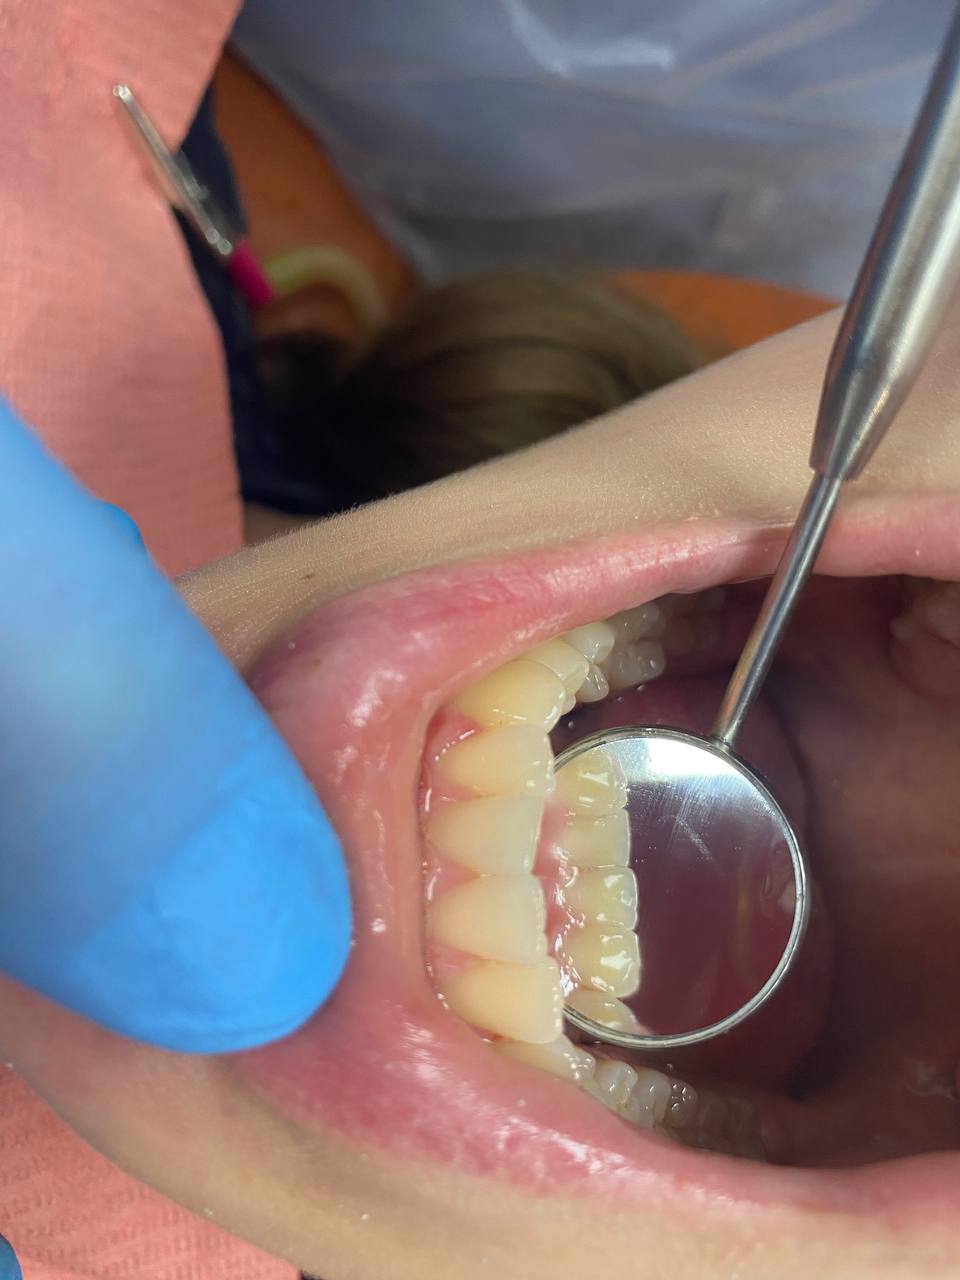

Снятие зубных отложений и зубного камня

Профессиональная гигиена полости рта играет важную роль в поддержании общего здоровья полости рта и предотвращении развития различных заболеваний!

Ультразвуковая чистка зубов - снятие зубного камня с помощью ультразвукового скайлера.